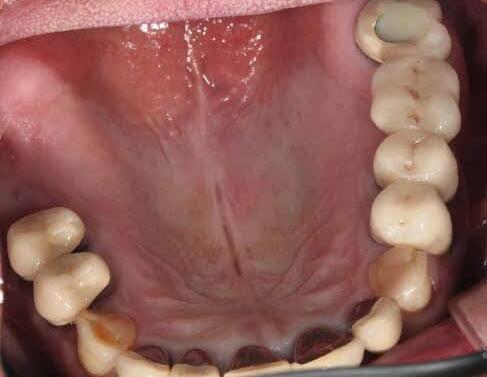

Restoring incisal wear and closing diastema with G-aenial A’CHORD. Courtesy of: Dr Aleksandra Slacan, Poland

Reshaping of teeth and diastema closure with G-aenial A’CHORD. Courtesy of: Dr Andres Silva, Spain